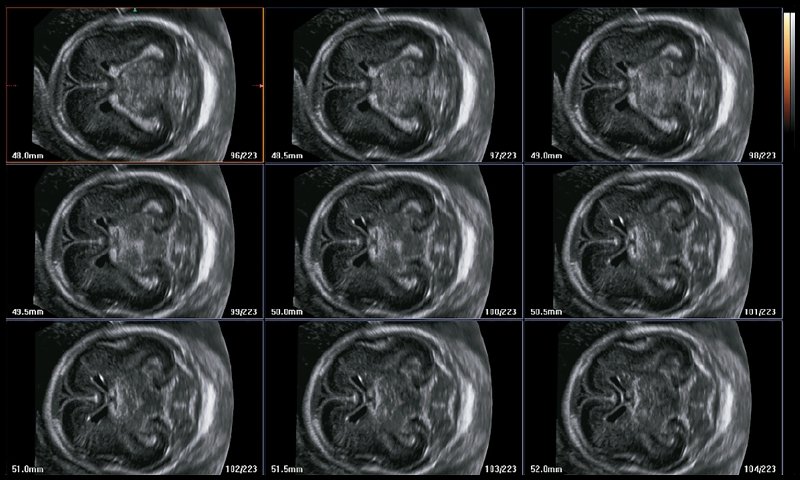

MultiSlice View (MSV) - многосрезовый вид

С помощью MultiSlice View в необходимой плоскости автоматически получают несколько параллельных срезов. Оператор может изменять исходную плоскость и толщину среза (от 0,5 до 5 мм) и выбирать количество отображаемых на экране изображений (1 x 1, 2 x 1, 3 x 2, 4 x 3 или 6 x 4). К тому же, как и во всех этих приложениях, изображения можно вращать в разных направлениях и увеличивать (рис. 3, 4).

Во II триместре 3D УЗИ может быть полезно для визуализации сагиттальной плоскости в мозге плода, позволяющей оценить мозолистое тело, червь мозжечка и другие срединные структуры. Оно также позволяет проводить аксиальные и фронтальные срезы позвоночника. Кроме того, его применяют при оценке извилин коры и борозд головного мозга плода. Чаще всего с этой целью применяют MPR, OV и ее вариации, а также MSV (рис. 14). При оценке поверхности тела можно получить высокоинформативные изображения.